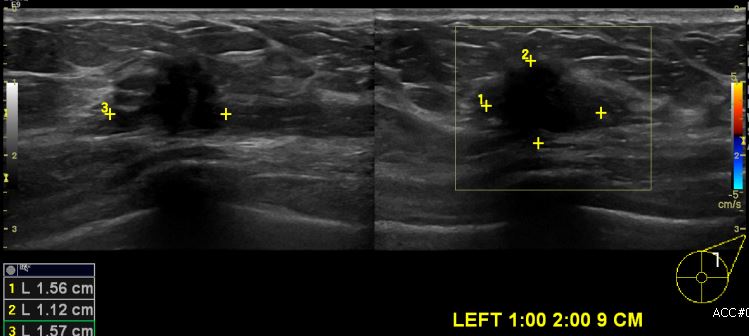

상기환자 건강검진상 이상 소견으로 내원하신 40대 여성분으로 초음파시행후  좌측

1:00 ~2:00 방향에서 9cm 떨어진 거리의 의심 스러운 혹 조직검사 시행하여 좌측 침윤성

유관암 진단 되었습니다.